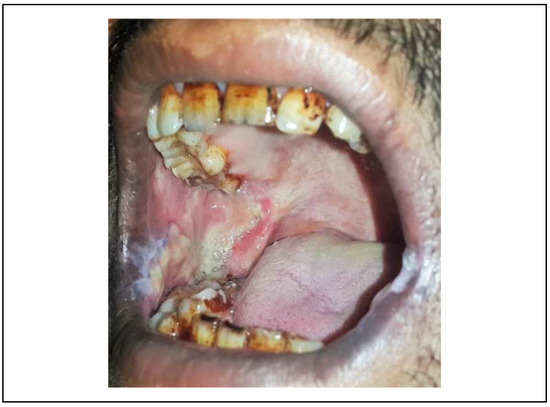

Inclusion criteria were patients with restricted mouth opening of <20 mm (stage III and IV) (Figure 1); patients having painful ulceration, burning sensation, intolerance to spices, a habit of betel nut or tobacco chewing, and histopathological features suggestive of OSMF; and patients with regular follow-up records. Patients with an ulceroproliferative growth picked up on palpation or ultrasonography, suspected to be malignant, patients with mouth opening of more than 25 mm and a mild form of mucositis, and patients without regular follow-up were excluded from the study. Both groups were evaluated for predictor variables like preoperative interincisal mouth opening (in millimeters) and preoperative oral commissural width (in millimeters) from Chelion (the most lateral point of labial fissure) of the right side to Chelion on left side. The outcome variables were postoperative IIMO as assessed by measuring the interincisal distance in millimeters, postoperative commissural width, and extraoral scar formation as analyzed by the Stony Brook Scar Assessment Scale[5] which is an objective assessment (Figure 2).

Figure 1. Preoperative profile.